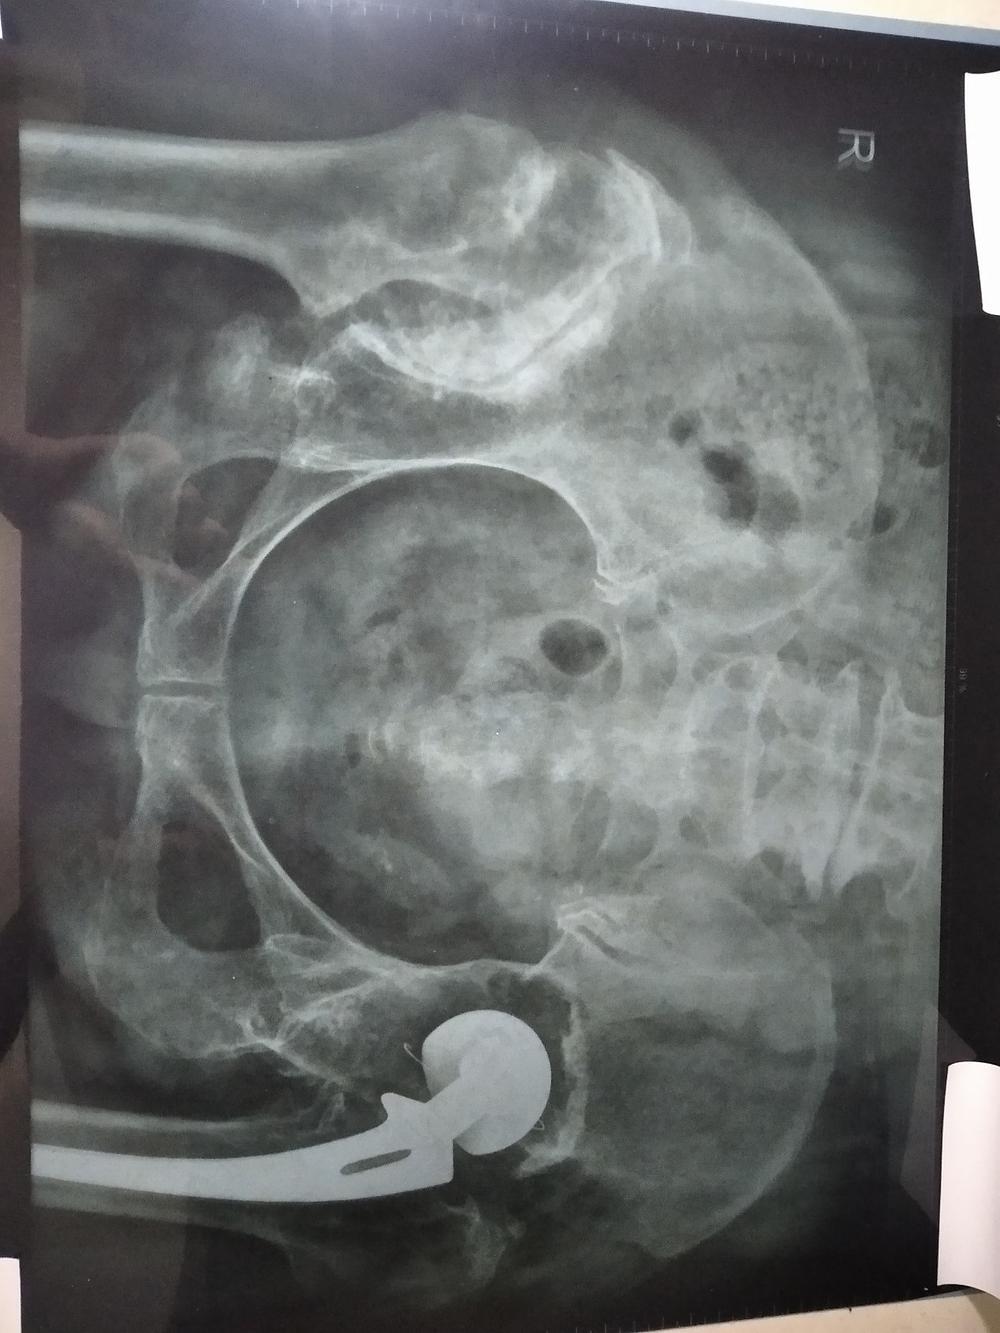

Nakon rendgenskog snimka urađenog u bolnici 21. marta ove godine, zaključak i sliku sam uvrstila ovdje.

Na slici se vidi da acetabulum desnog zgloba kuka postaje plići i gušći, a glava femura se pomjera prema gore i formira pseudartrozu. Glava femura je ravna i široka, a gustina je veća. Nakon vještačke zamjene zgloba lijevog kuka, preostala koštana struktura je bila dobra, trabekularna kost čista, zglobni prostor normalan, a zglobna površina glatka.